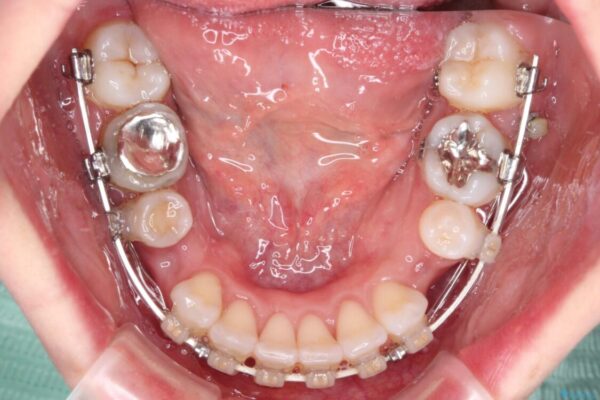

治療途中

• 【モニター】出っ歯と咬み合わせを改善 ワイヤー装置の抜歯矯正 治療途中画像